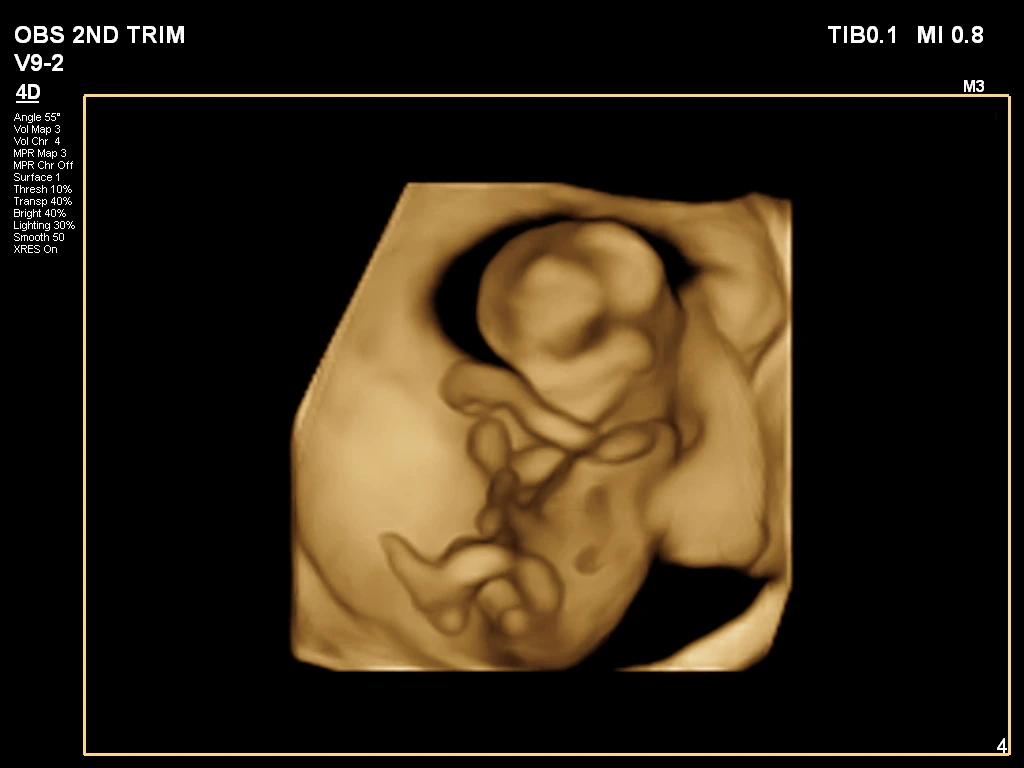

🔹 3D / 4D Ultrasound

3D/4D Ultrasound provides a clear and real-time view of your baby inside the womb. While 3D shows detailed images, 4D allows you to see live movements like smiling or yawning. It enhances bonding between parents and baby while also helping doctors assess physical development. Experience advanced 4D ultrasound in Kathmandu for a memorable and informative pregnancy journey.